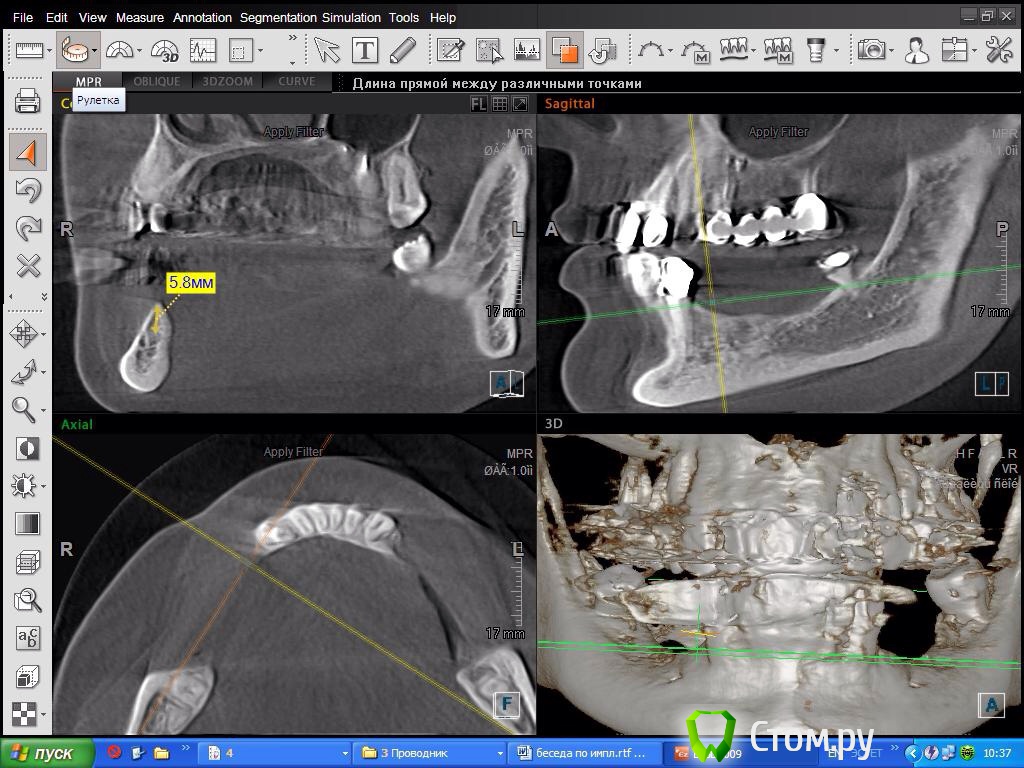

SDC Опубликовано 8 октября, 2014 Поделиться Опубликовано 8 октября, 2014 Склоняюсь в 4 кв делать консоль! Спасибо за мнениеПосмотрим срезы на уровне 2 премоляра? Получится ли имплантировать в этом месте? Ссылка на комментарий

DoktorDre Опубликовано 8 октября, 2014 Автор Поделиться Опубликовано 8 октября, 2014 Посмотрим срезы на уровне 2 премоляра? Получится ли имплантировать в этом месте?Получится, после ламинатов) Ссылка на комментарий